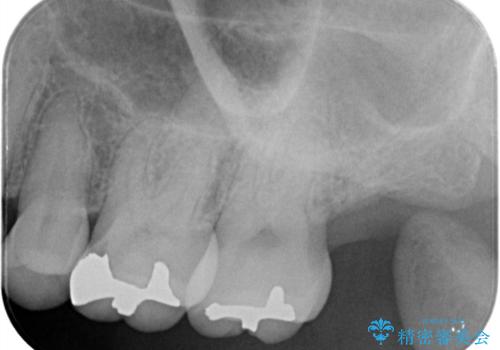

左上6番に入っている保険適応のメタルインレーと歯質との境目(近心側室エリア)に不適部位を認め、そのくぼみに汚れが停滞しやすい状態となっていました。

適合性・審美性を考慮し、セラミックインレーでのやり替えとなりました。